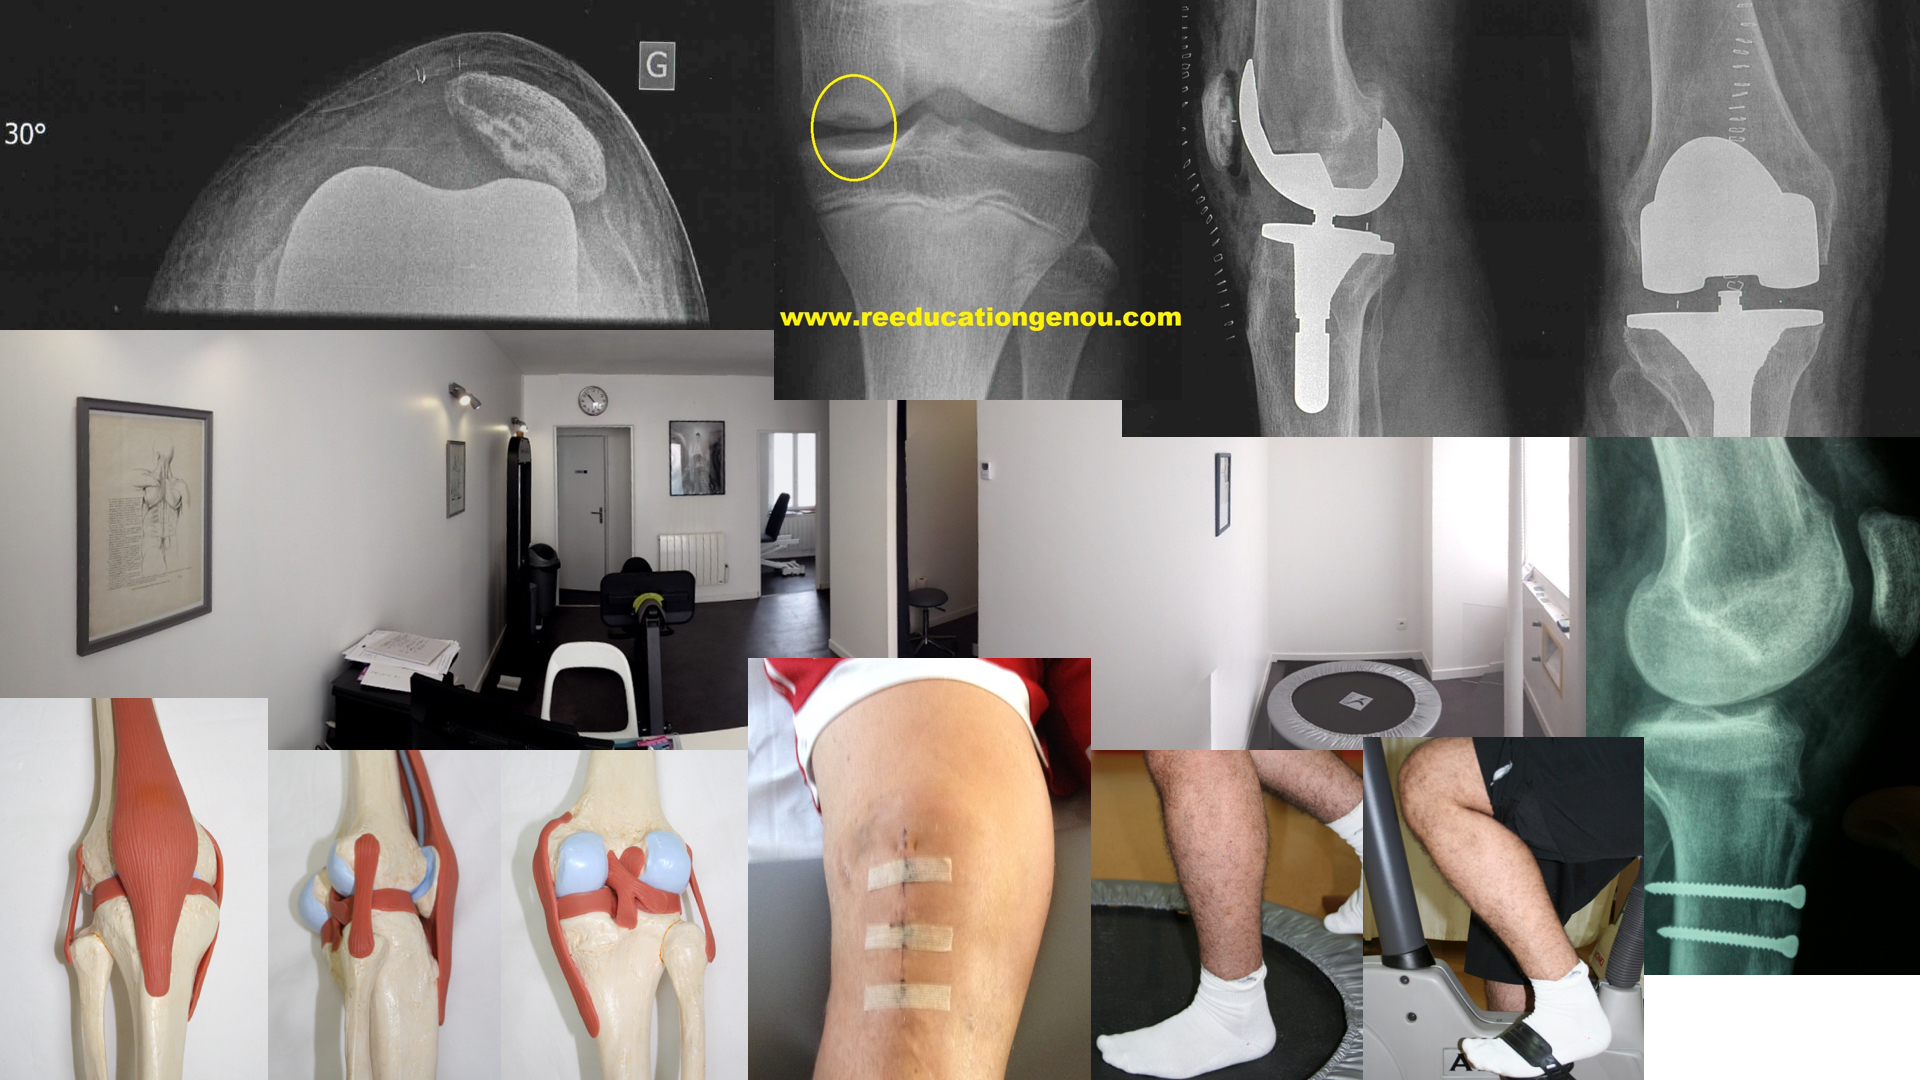

La rotule

Définition du syndrome rotulien ou syndrome fémoro patellaire

Syndrome rotulien ou syndrome fémoro patellaire

Le syndrome rotulien ou syndrome fémoro patellaire est un ensemble de signes cliniques et douloureux décrits par le patients.